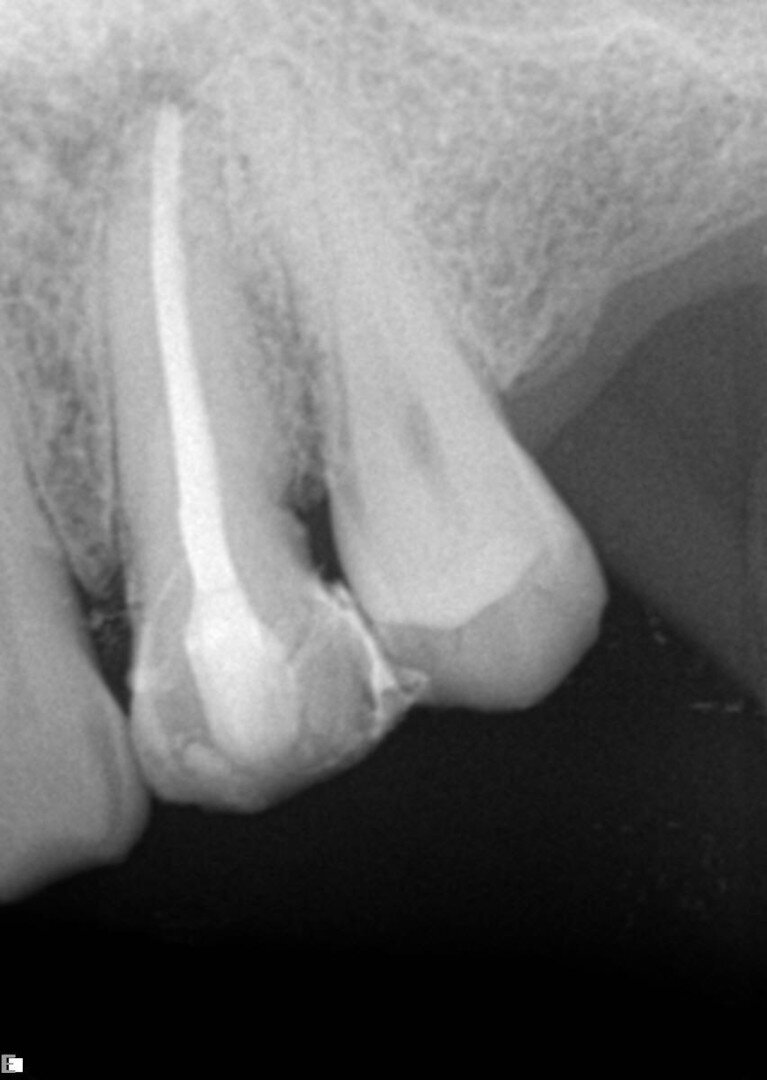

U ovom prvom primeru, pacijent je upućen na lečenje sinusnog trakta maksile (Sl. 1). Unutar fistule je postavljen konus od gutaperke, koji pokazuje put do mesta infekcije. Ovo je bio jednostavan slučaj, pripremljen korišćenjem Traverse turpije 25/0.08 u gornjem delu, nakon čega je nastavljen rad sa K-File 10 (Kerr) da bi se odredila radna dužina, a zatim je 40/0.06 Traverse file doveden do radne dužine. Naravno, tretman je podrazumevao kompletnu hemijsku pripremu i 3D obturaciju prostora kanala korena (Sl. 2).